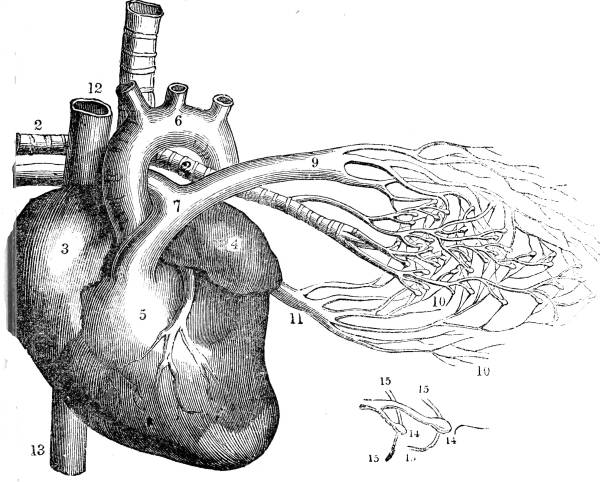

1. The trachea. 2. The right and left bronchus; the left

bronchus showing its division into smaller and smaller

branches in the lung, and the ultimate termination of the

branches in the air vesicles. 3. Right auricle of the heart.

4. Left auricle. 5. Right ventricle. 6. The aorta arising from

the left ventricle, the left ventricle being in this diagram

concealed by the right. 7. Pulmonary artery arising from

the right ventricle and dividing into, 8. The right, and

9. The left branch. The latter is seen dividing into smaller

and smaller branches, and ultimately terminating on the

air vesicles. 10. Branches of one of the pulmonary veins

proceeding from the terminations of the pulmonary artery

on the air vesicles, where together they form the net-work

of vessels termed the Rete Mirabile. 11. Trunk of the

vein on its way to the left auricle of the heart. 12.

Superior vena cava. 13. Inferior vena cava. 14. Air vesicles

magnified. 15. Blood-vessels distributed upon them.